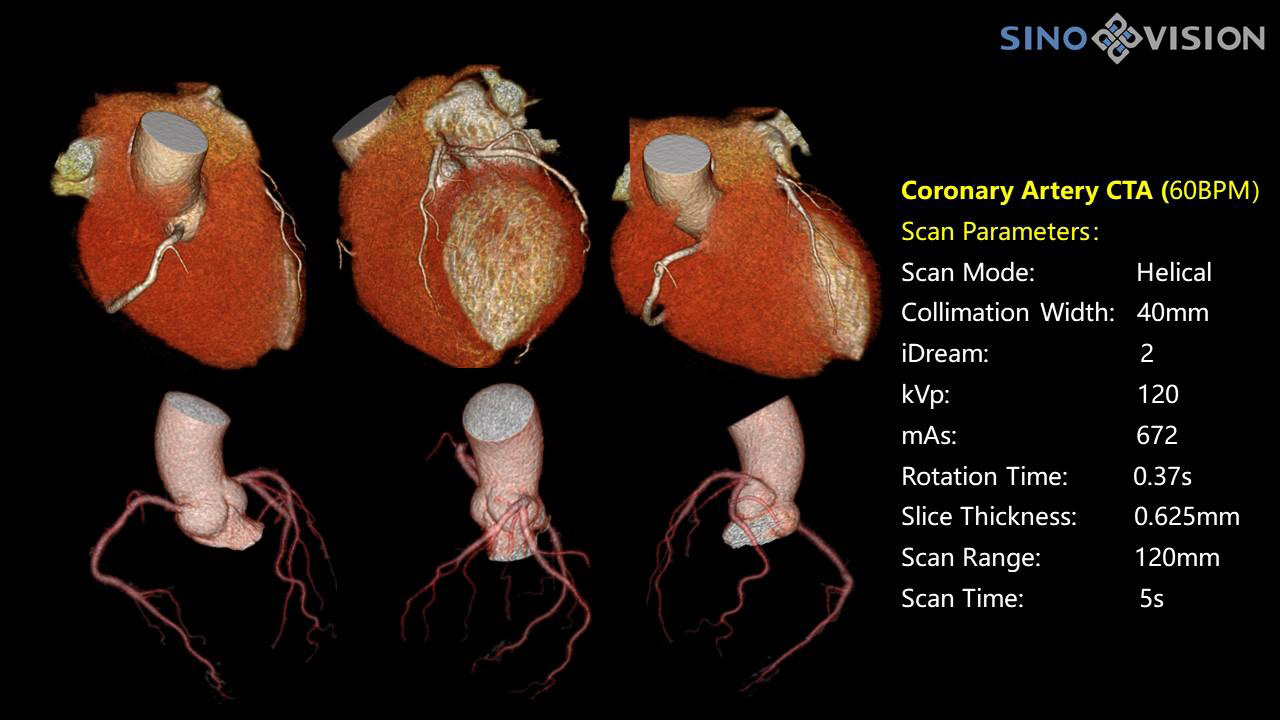

InsitumCT 768 является вершиной нового поколения широкоапертурных широкополосных компьютерных томографов. Этот КТ-сканер обеспечивает 128 срезов КТ при апертуре 76 см, увеличивая производительность визуализации до 21 л/см, способствуя точной диагностике и лечению заболеваний и значительно улучшая клинические характеристики и масштабируемость. Обеспечивает получение изображений высокого разрешения при низкой дозе облучения.

Компьютерный томограф Insitum CT 768 – старшая модель в линейке SinoVision Insitum. Еще более быстрый и еще более мощный, он значительно повышает пропускную способность кабинета КТ, обеспечивая при этом высококачественные исследования даже в самых сложных случаях практически во всех областях, включая кардиологию, исследования сосудистой системы, онкологию. Имеет специализированный педиатрический протокол исследования, минимализирующий лучевую нагрузку на ребенка.

Специализированная технология RTF позволяет уменьшать артефакты движения сердца, обеспечивая максимально точное клиническое изображение.

- Количество срезов: 128

- Толщина среза: 0.625 мм

Характеристики сканирования

- Минимальное время одного оборота рентгеновской трубки: От 0.37 до 2 сек

- Коронарный анализ

- Ретроспективный режим сканирования с ЭКГ-синхронизацией

- Проспективный режим сканирования с ЭКГ-синхронизацией

- Режим последовательного сканирования c ЭКГ-синхронизацией и без ЭКГ-синхронизации